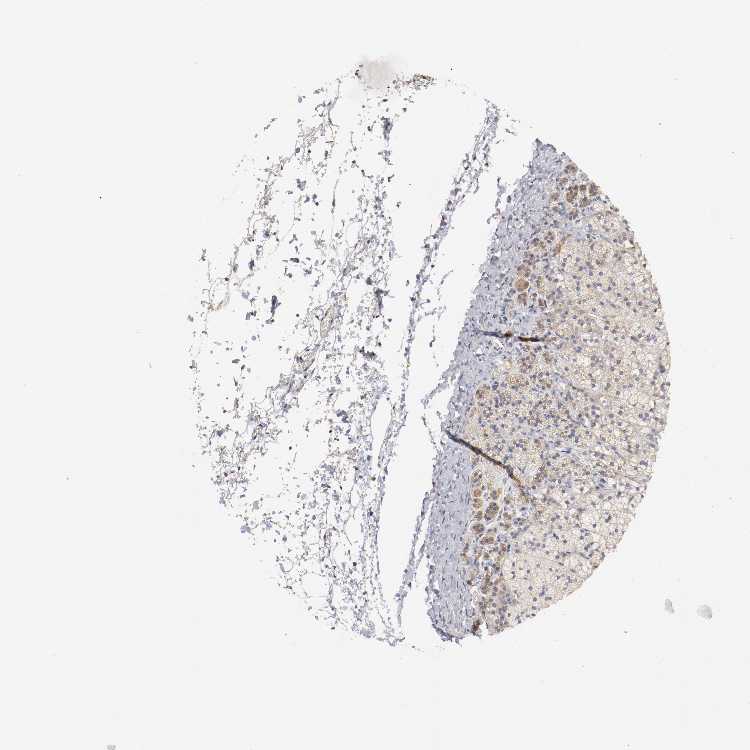

ADRENAL GLAND - Antibody stainingi

Antibody staining in the annotated cell types in the current human tissue is reported as not detected, low, medium, or high, based on conventional immunohistochemistry profiling in selected tissues. This score is based on the combination of the staining intensity and fraction of stained cells.

Each image is clickable and will lead to virtual microscopy that enables deeper exploration of all samples and also displays staining intensity scores, fraction scores and subcellular localization as well as patient and tissue information for each sample.

Antibody HPA009972Antibody HPA010634Antibody CAB004603

Glandular cells MediumLowMedium